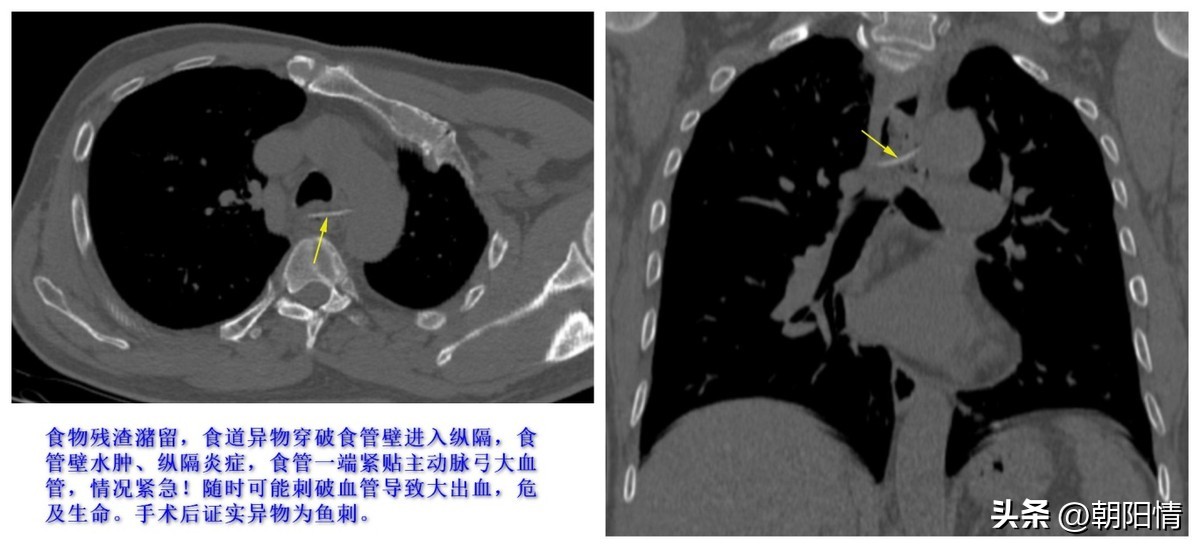

(2)食管胸上段异物

Case4:食管胸上段鱼骨

鱼骨下行到心脏大血管附近,非常凶险!